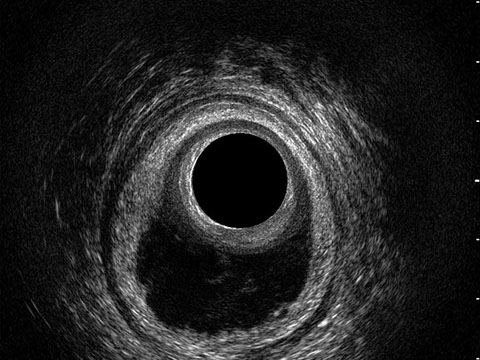

Le principali indicazioni all’esecuzione di tale esame sono lo studio dell’integrità delle strutture muscolari nei casi di incontinenza fecale, lo studio topografico dei processi settici perianali (ascessi e fistole) e lo studio dei processi proliferativi epiteliali (carcinoma anale).

Sezione Longitudinale 3D con Tramite Fistoloso Intersfinterico Basso Anteriore Semplice

Proctal dispone di apparecchiatura per ecografia endoanale 3D con sonda rotante.